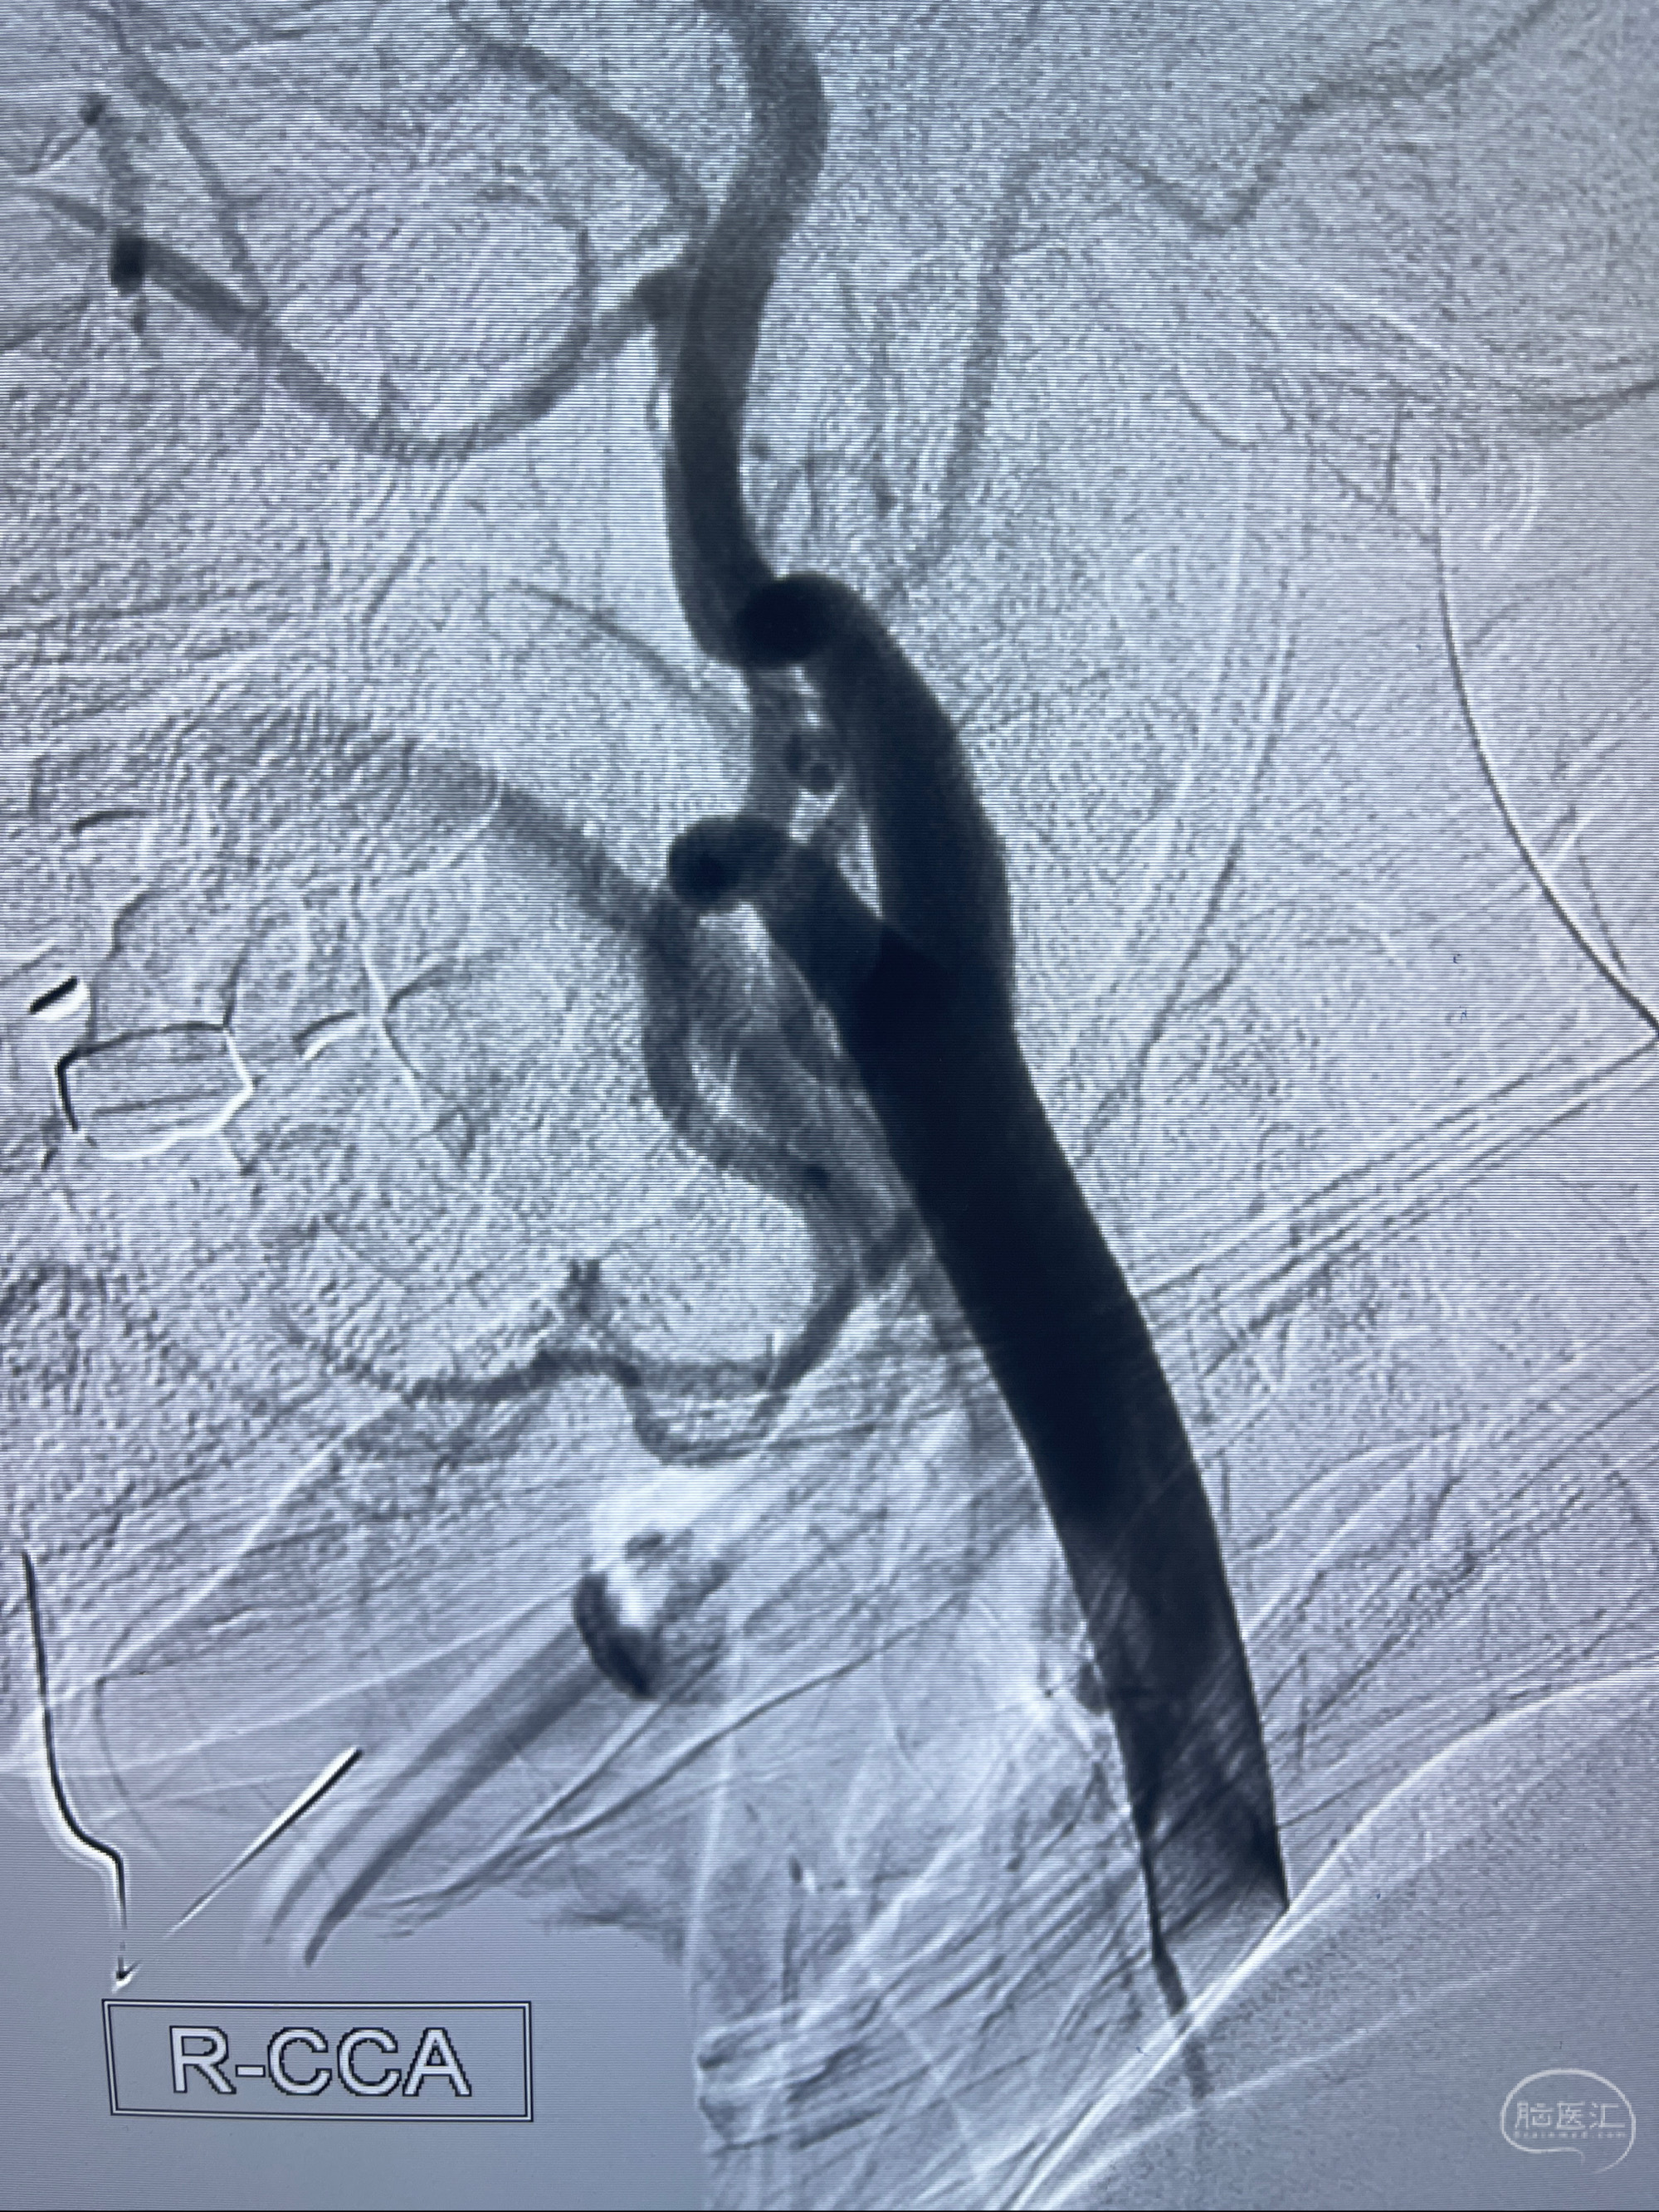

2023-02-02 沛县人民医院 头颅CTA:大脑动脉环发育变异,头颈部动脉粥样硬化,双侧颈内动脉及椎动脉颅内段多发狭窄;

2023-02-15DSA